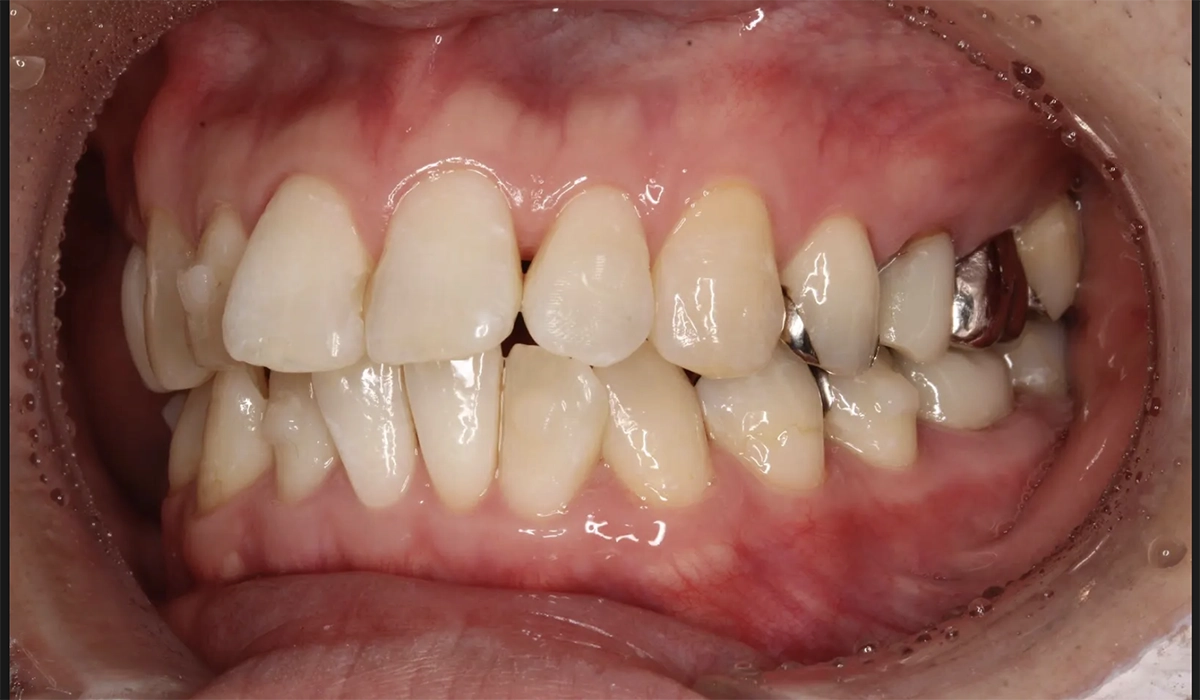

術前:正面

術後:正面